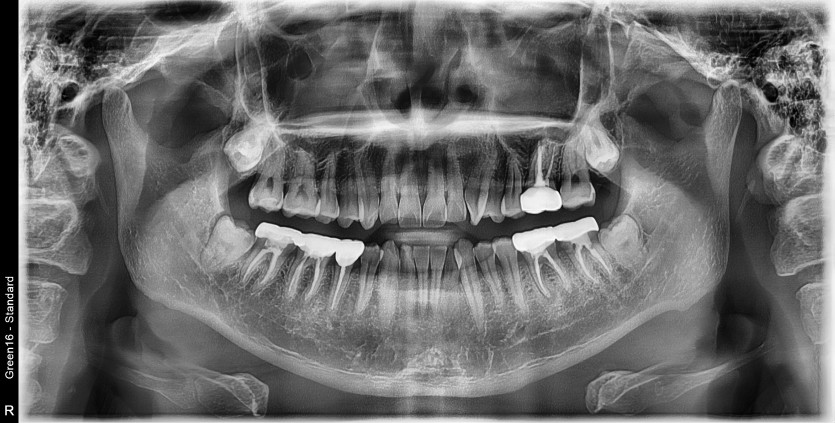

#48 사랑니 발치

구강 외과 전문의가 당일 발치했습니다.